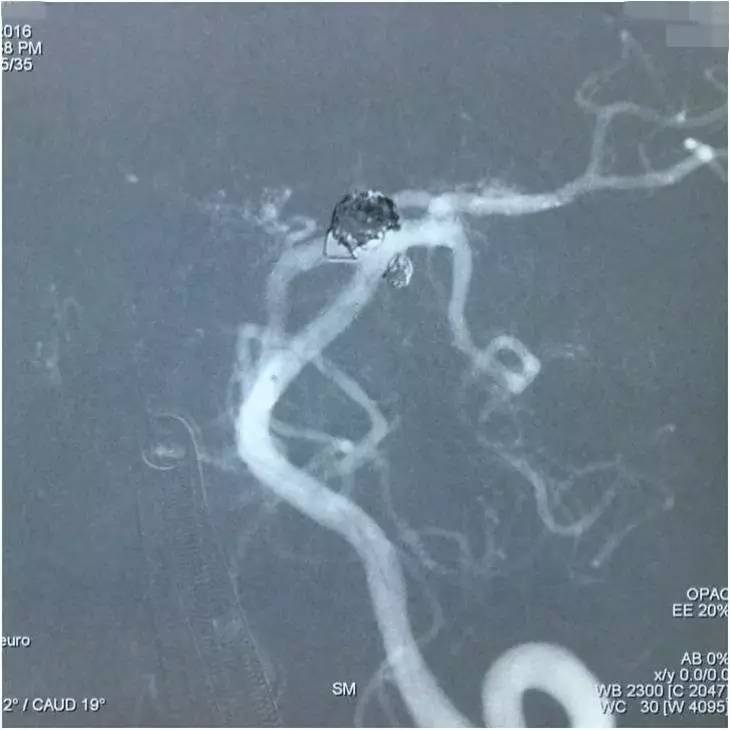

▼左椎动脉工作位造影,可以清晰暴露基底动脉顶端动脉瘤及其子瘤、左小脑上动脉瘤。

▼Headway17导入左PCA P2段,用于备放LVIS JR支架;Echelon10微导管送入基底动脉顶端动脉瘤瘤腔内,送入第一枚弹簧圈QC-4-12-3D,弹簧圈送出约一半长度,在瘤腔内盘旋,一定程度上能有助于防止后续释放的支架陷入瘤腔。

▼经预置的Headway17送入LVIS JR 3.5*23支架,跨瘤颈释放入左PCA-基底动脉内,蒙片显示支架张开良好。